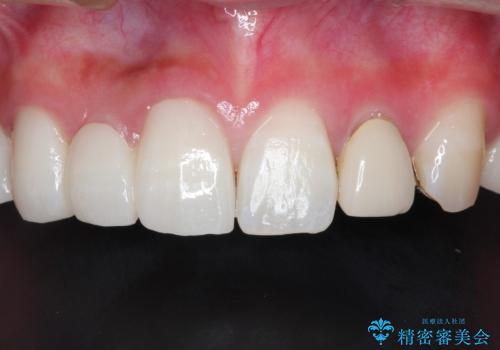

前歯にレジン前装冠(保険内)が装着されており、自然な透明感がありません。

オールセラミックによるやりかえを行いました。

色調もまわりの歯に合わせて、形態も患者様のご希望に沿うように製作させていただきました。